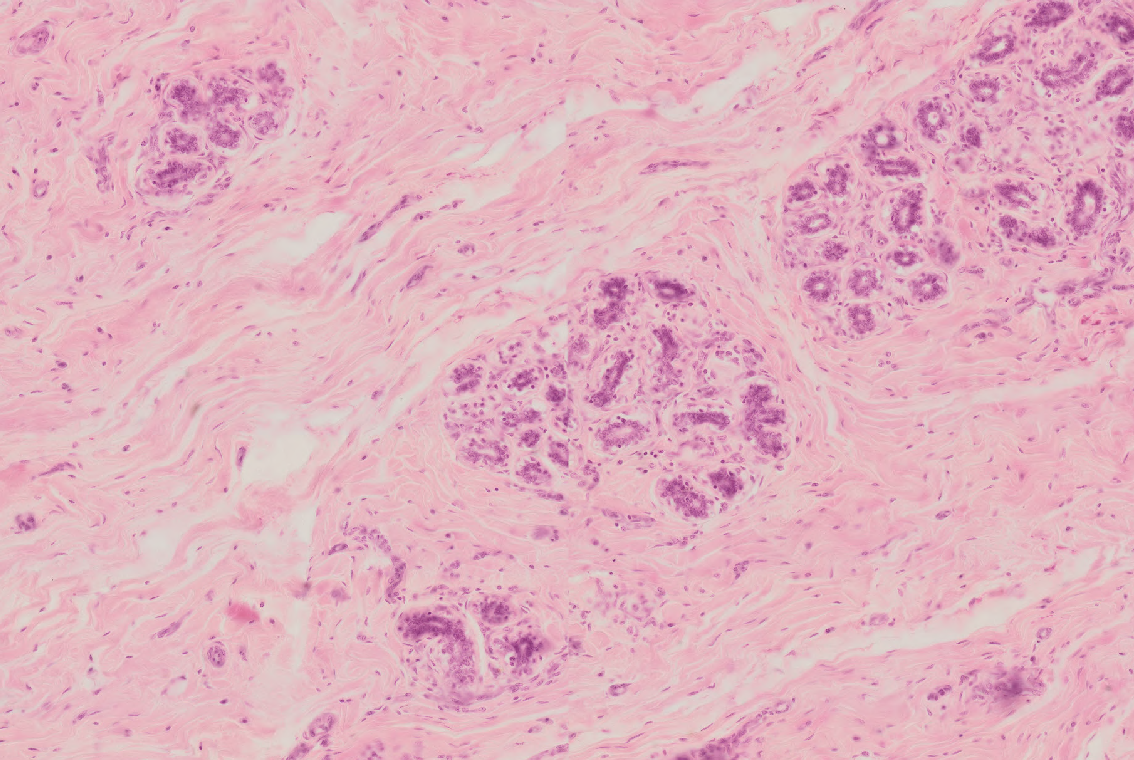

11 Which structure is highlighted by green color on the specimen of skin (hematoxylin-eosin)?

Skin Sweat.png

Ductus of an aromatic gland

Ductus of a sebaceous gland

Ductus of a sweat gland

Hair follicle